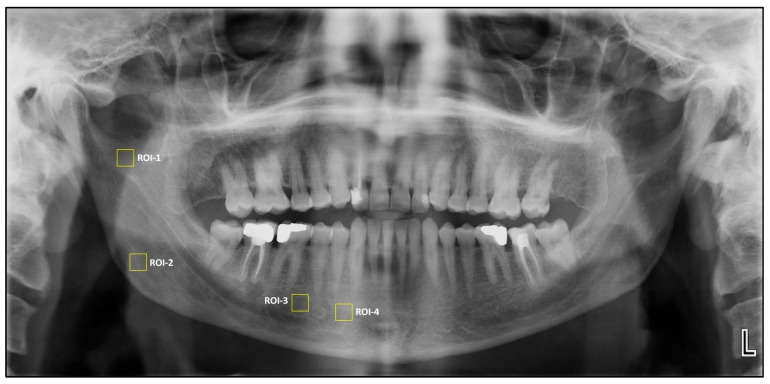

Methods: This retrospective study analyzed panoramic radiographs from 200 individuals, comprising 40 patients in each of the four endocrine disorder groups and 40 healthy controls. Fractal dimension and histogram-based pixel intensity analyses were conducted using ImageJ™ (version 1.53) software. Four standardized regions of interest (ROI) were evaluated on the right mandible, and statistical comparisons were conducted across groups using one-way analysis of variance (ANOVA), t-test, Mann-Whitney U, and Spearman correlation analyses.

Results: Age and gender distributions did not differ significantly between groups. FD analysis revealed a significant reduction at ROI1 in the hyperthyroidism group compared to controls (p = 0.018); however, no other significant FD differences were observed among the remaining groups or ROIs. A significant positive correlation was found between FD and histogram values at ROI1 and ROI2 (p < 0.001), while pixel intensity values did not differ significantly across groups in any ROI.